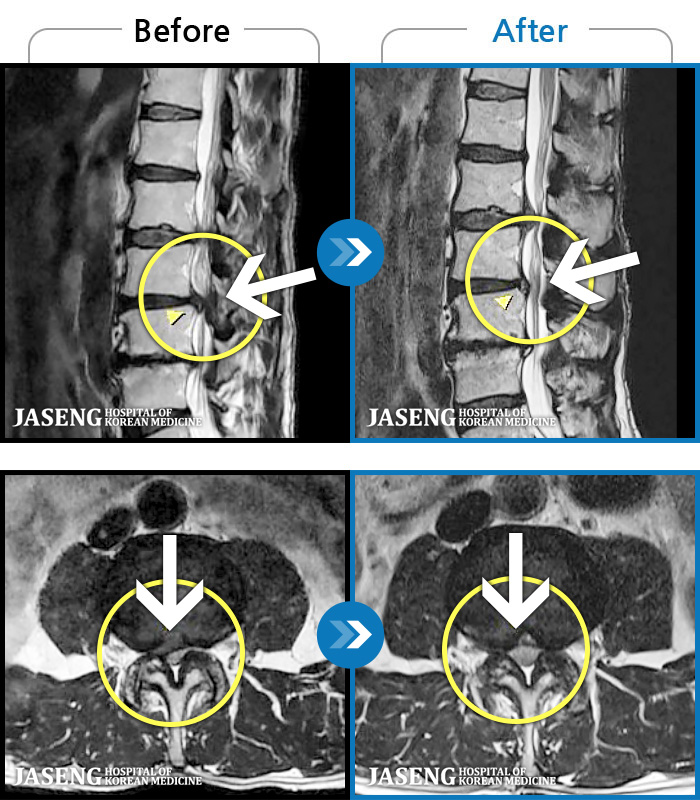

- MRI ġ

MRI ġ

1,304 MRI ũ ʸ Ȯϼ.

Ƹ ϰ ־.